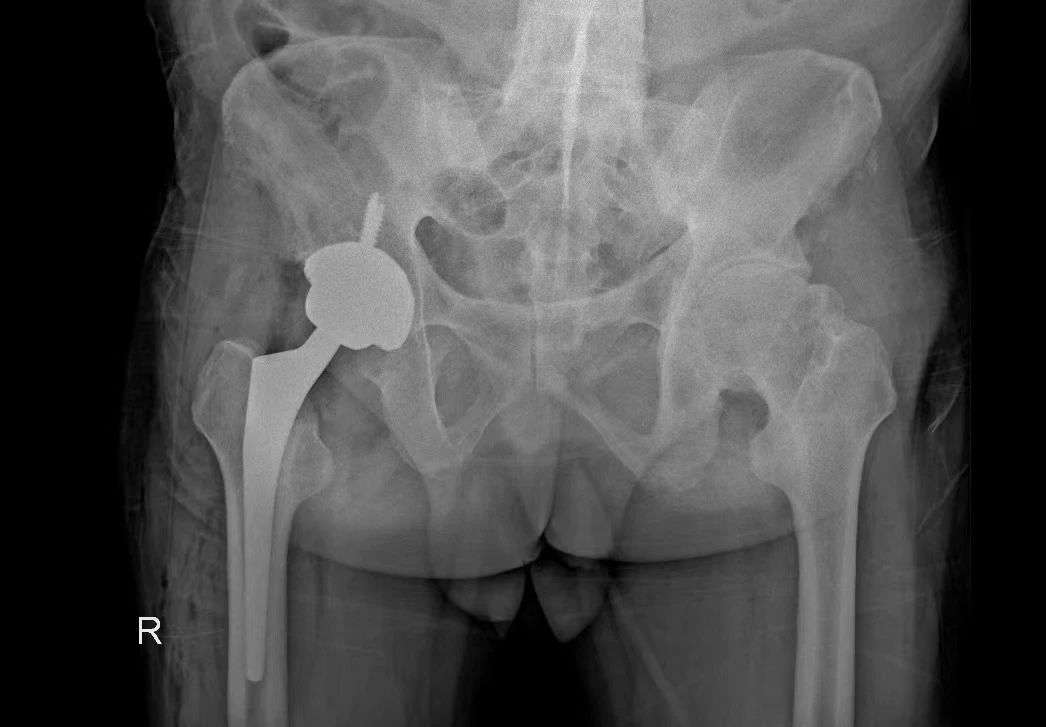

術后,在科室醫(yī)護人員及康復團隊的精心照料下,患者術后12小時可以下地走路,術后一周棄拐行走恢復良好并順利康復。

術后平片